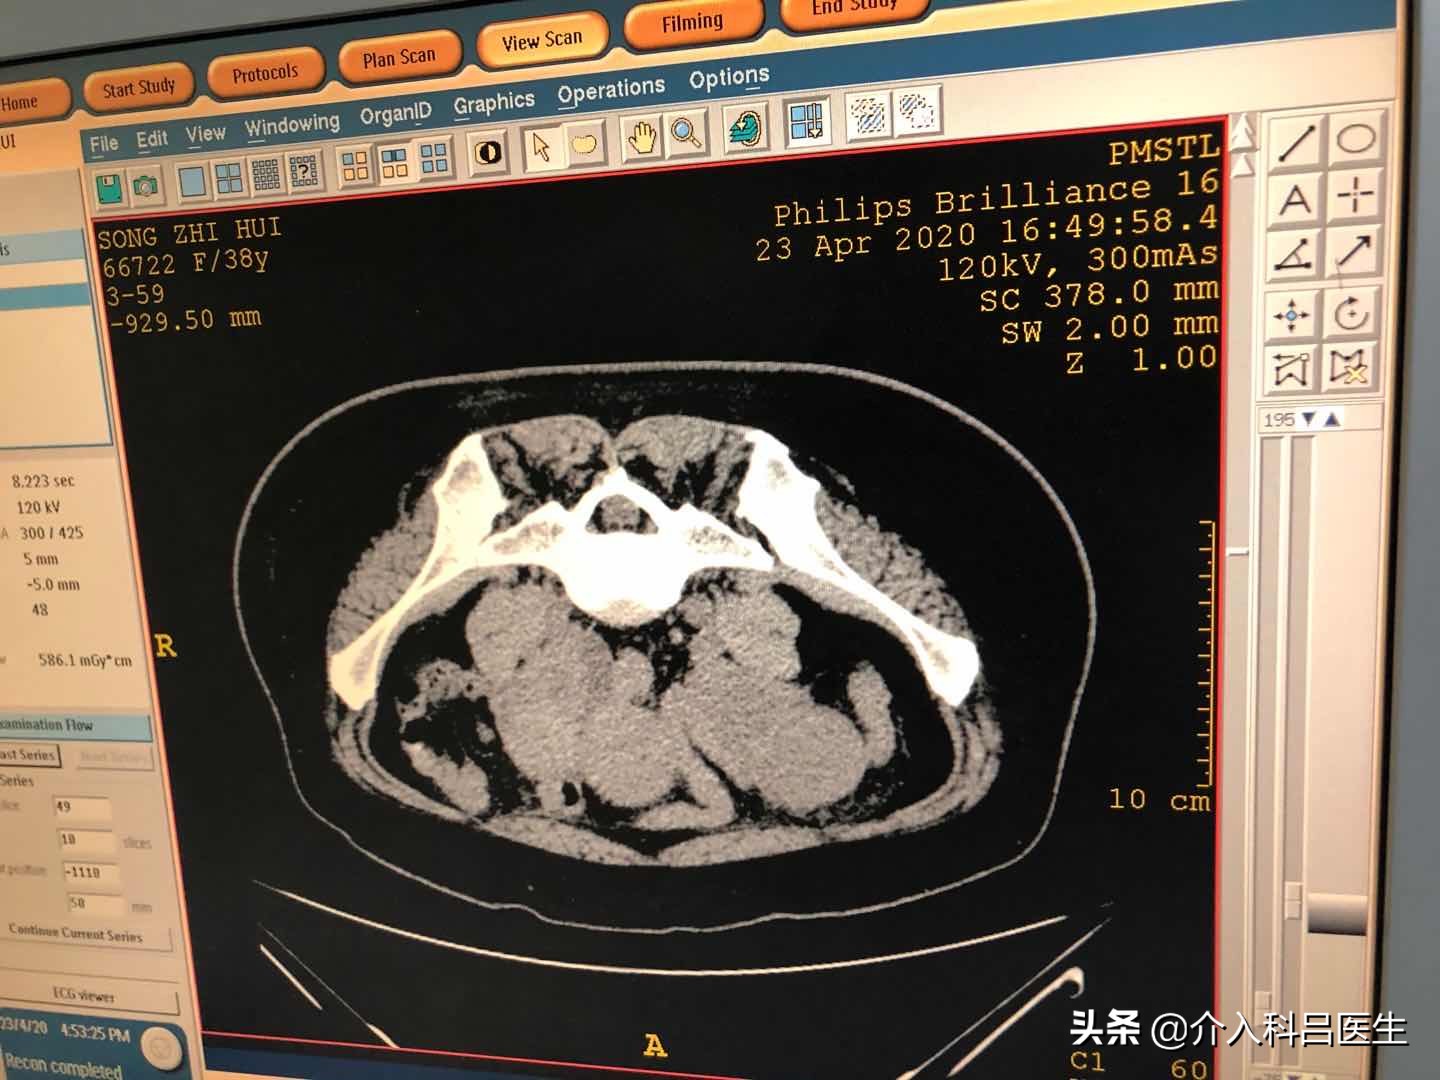

做ct的时候也可以看到患者因为腺肌症,子宫体积非常大,这样的子宫环境当然不容易受孕。